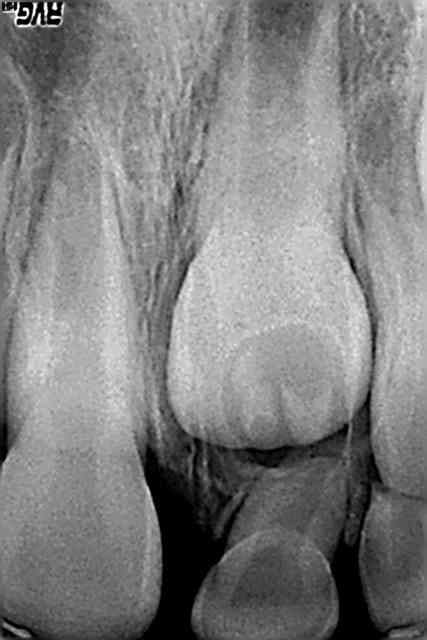

Voici un cas clinique de pédodontie:

Enfant de 4 ans et 7 mois.

Découverte fortuite lors du brossage par ses parents. Pas de douleurs signalées par l'enfant. Pas de souvenir de traumatisme pas de témoins mais l'enfant est un peu "cascadeur". Enfant en bonne santé générale.

Sur la radio, on observe une image de résorption latérale.

Pas de douleurs à la palpation ou au contact dentaire de la 51. Mobilité peut être un peu supérieure à la mobilité physiologique entre le pouce et l'index mais difficile a évaluer.

Quel est votre diagnostic? Quel traitement mettriez vous en place? quel est votre pronostic?